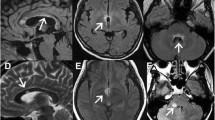

Group 1 and Group 2

‘MS-like’ and ‘spinal MS-like’ patients did not differ significantly between each other in terms of normal-appearing white matter tract integrity (Fig. 3A, 3B) or atrophy measures in the brain but the latter group had a lower mean cross-sectional area in the cervical spinal cord (57.7 ± 6.8 vs. 61.4 ± 4.3, non-significant, Fig. 3C). Both groups combined also had a trend for higher R2* values in the thalamus compared to patients from NMO-like groups (21.9 ± 1.2 vs. 20.9 ± 1.0, Table 3). Only patients from the MS-like groups had cortical lesions (Fig. 4A) and, as expected, these were more common in patients with white matter brain lesions (Group 1) than in patients with predominantly spinal MS-like disease (Group 2).

Fractional anisotropy in the corpus callosum (A) and corticospinal tracts (B) in each identified subgroup. Group 4 shows significantly lower fractional anisotropy in the corpus callosum as compared with other groups (***p < 0.001), but no between-group difference is observed in corticospinal tracts. (C) Mean spinal cord cross-sectional area averaged across all eight cervical segments in four identified subgroups. Group 4 had significantly more atrophy than Group 3 (*p = 0.01). Statistically significant differences are marked with asterisks

Different aspects of cortical pathology are shown across four groups (A) mean number of cortical lesions, (B) mean cortical thickness, (C) mean diffusivity in the cortex. Mean diffusivity in the cortex was significantly higher in Group 4 as compared with Group 3 (*p = 0.02, marked with an asterisk)

Group 3

Despite high proportion of previous LETM history (60%) “classic NMO-like” patients did not appear to have spinal cord atrophy and had significantly higher mean cervical spinal cord cross-sectional area when compared to “NMO-like with brain involvement” patients (65.7 ± 5.1 vs. 53.1 ± 6.5, p = 0.01, Fig. 3B). “Classic NMO-like” patients also had high cortical thickness and absence of cortical lesions, which all suggested absence of cortical pathology in this group (Fig. 4).

Group 4

Given that low fractional anisotropy in normal-appearing white matter tracts (with the exclusion of the optic radiation) strongly contributed to the generation of “NMO-like with brain involvement” subgroup we analysed whether this difference is attributed to any particular white matter tract. Interestingly, we have found significant differences in fractional anisotropy in the corpus callosum when comparing between Group 4 and each of the three other groups (p < 0.001, Tukey’s test), but not in corticospinal tracts (Fig. 3, Table 3). Cerebral volumetric measures (total brain, basal ganglia, brainstem volume, cortical thickness) were generally lower in this group as compared to other groups but this was not statistically significant (Table 3). Importantly, patients from this group had significantly higher mean diffusivity in the cortex as compared with “classic NMO-like” and “spinal MS-like” patients (Fig. 4).